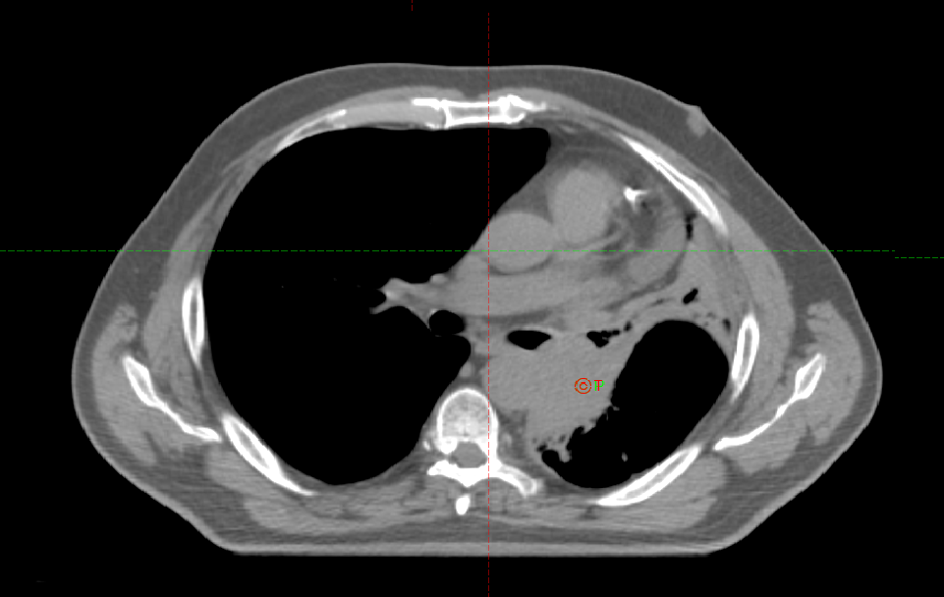

СВСТ от 8.08.2022

CBCT - конусно-лучевая компьютерная томография

08.08.2022 на СОД 22 Гр выполнена повторная

КТ- топометрия органов грудной клетки

с 21.07.2022 по 2.09.2022 проведен радикальный курс лучевой терапии на первичную опухоль легкого и ПЭТ позитивные лимфоузлы РОД 2 Гр СОД 60 Гр за 30 фракций с одновременной химиотерапией по схеме паклитаксел+карбоплатин, 4 введения еженедельно.

09.09.2022 по месту жительства выполнена КТ ОГК. Отмечается положительная динамика.

СВСТ от 02.09.2022